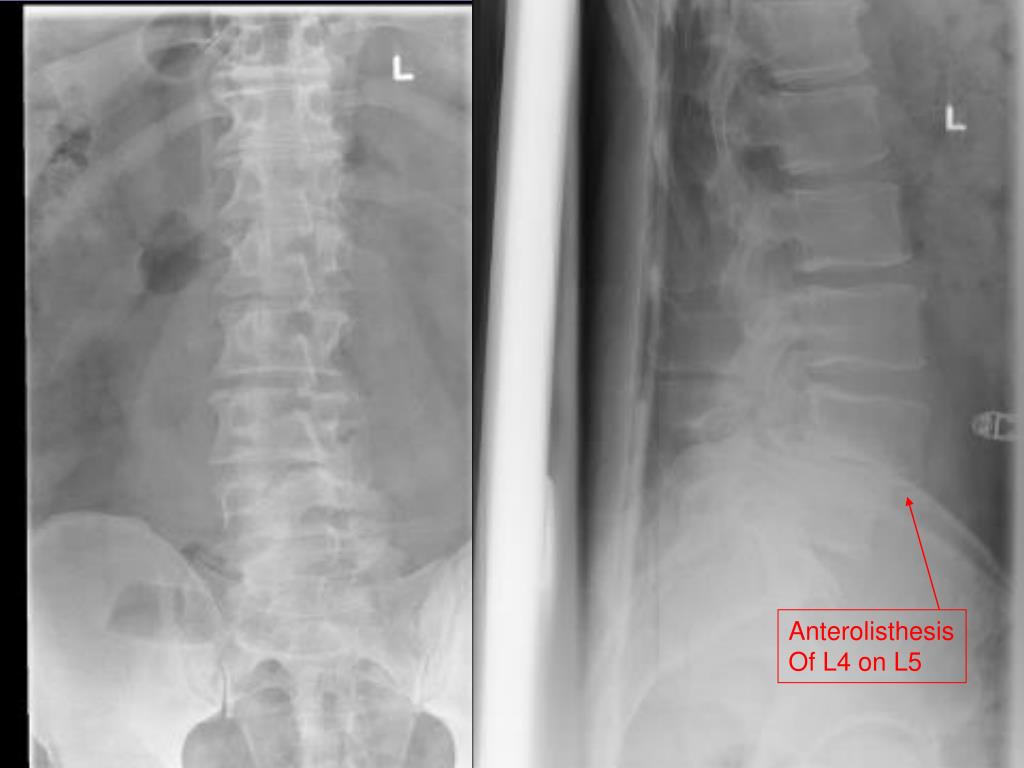

15. Case 2 • 46 yo male presents to ED after falling 12 feet off ladder while putting up Christmas lights c/o back pain

16. Anterolisthesis Of L4 on L5